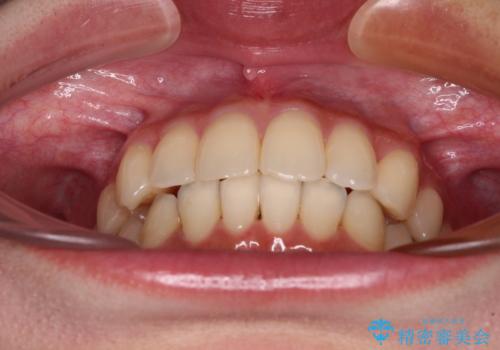

- 前歯のデコボコと強い咬みしめを気にして来院された患者様です。

インビザラインを用いて、前歯の叢生を解消するとともに、ディープバイトを改善していくこととしました。

海外へ転居する予定があったため、1日22時間以上の装着時間をしっかりと守っていただき、予定期間よりも早く、思っていた以上にきれいに仕上げることができました。